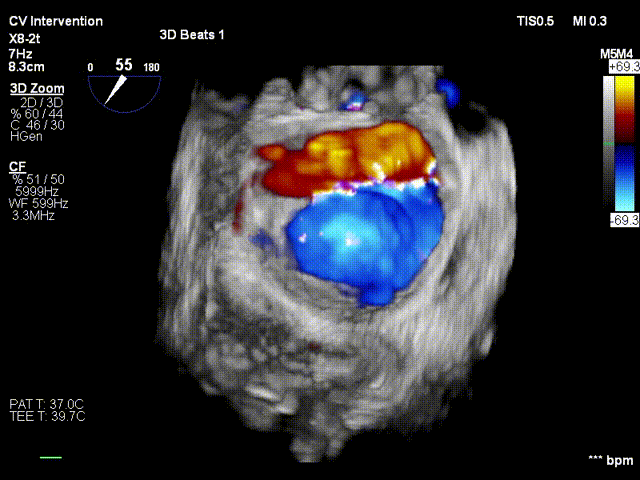

患者镇静麻醉状态,呼吸机辅助呼吸,ECMO+IABP循环支持,因右侧股静脉入路ECMO占用,遂行左侧股静脉入路,顺利穿刺房间隔,经导管测定左房压力为:41/-3/14mmHg。之后迅速送入经导管二尖瓣钳夹系统,予XTR准确地捕获二尖瓣叶,于A2/P2区域完成夹合,MR4+反流即刻减少至2+;再予NTR定位与残余反流区域,完成二次夹合,反流即刻较少至微量。术中DSA及TEE评估夹合器稳定,遂退出钳夹系统。测定左房压13/-3/1mmHg,较前明显下降,血流动力学稳定,撤处ECMO,保留IABP,手术成功。

患者术后当天回病房撤除IABP,第二天麻醉苏醒,第三天撤除呼吸机辅助呼吸,目前生命体征平稳,血压159/63mmHg,近日可转入普通病房。